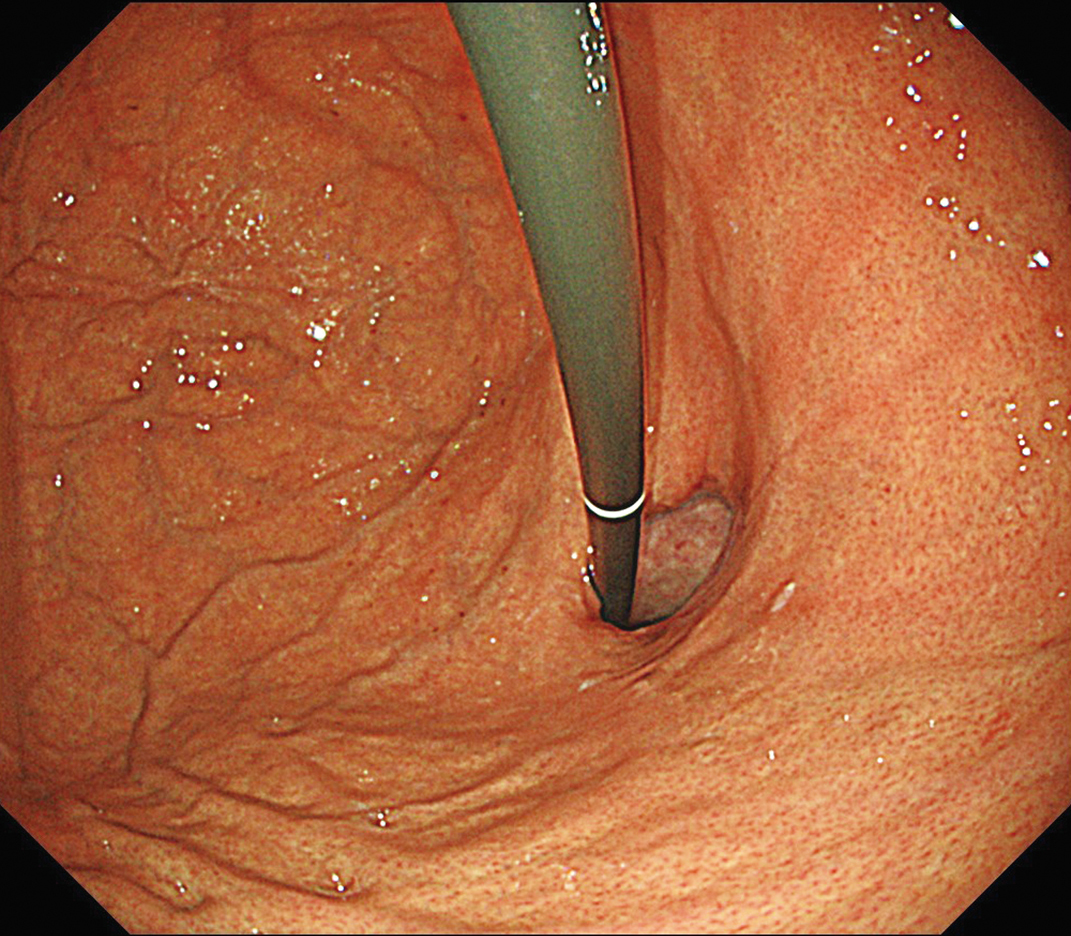

EVIS X1×GIF-1200N 症例画像

胃体部 見上げ観察 胃潰瘍症例

1視野で体下部から噴門部まで明るい視野での観察に貢献する